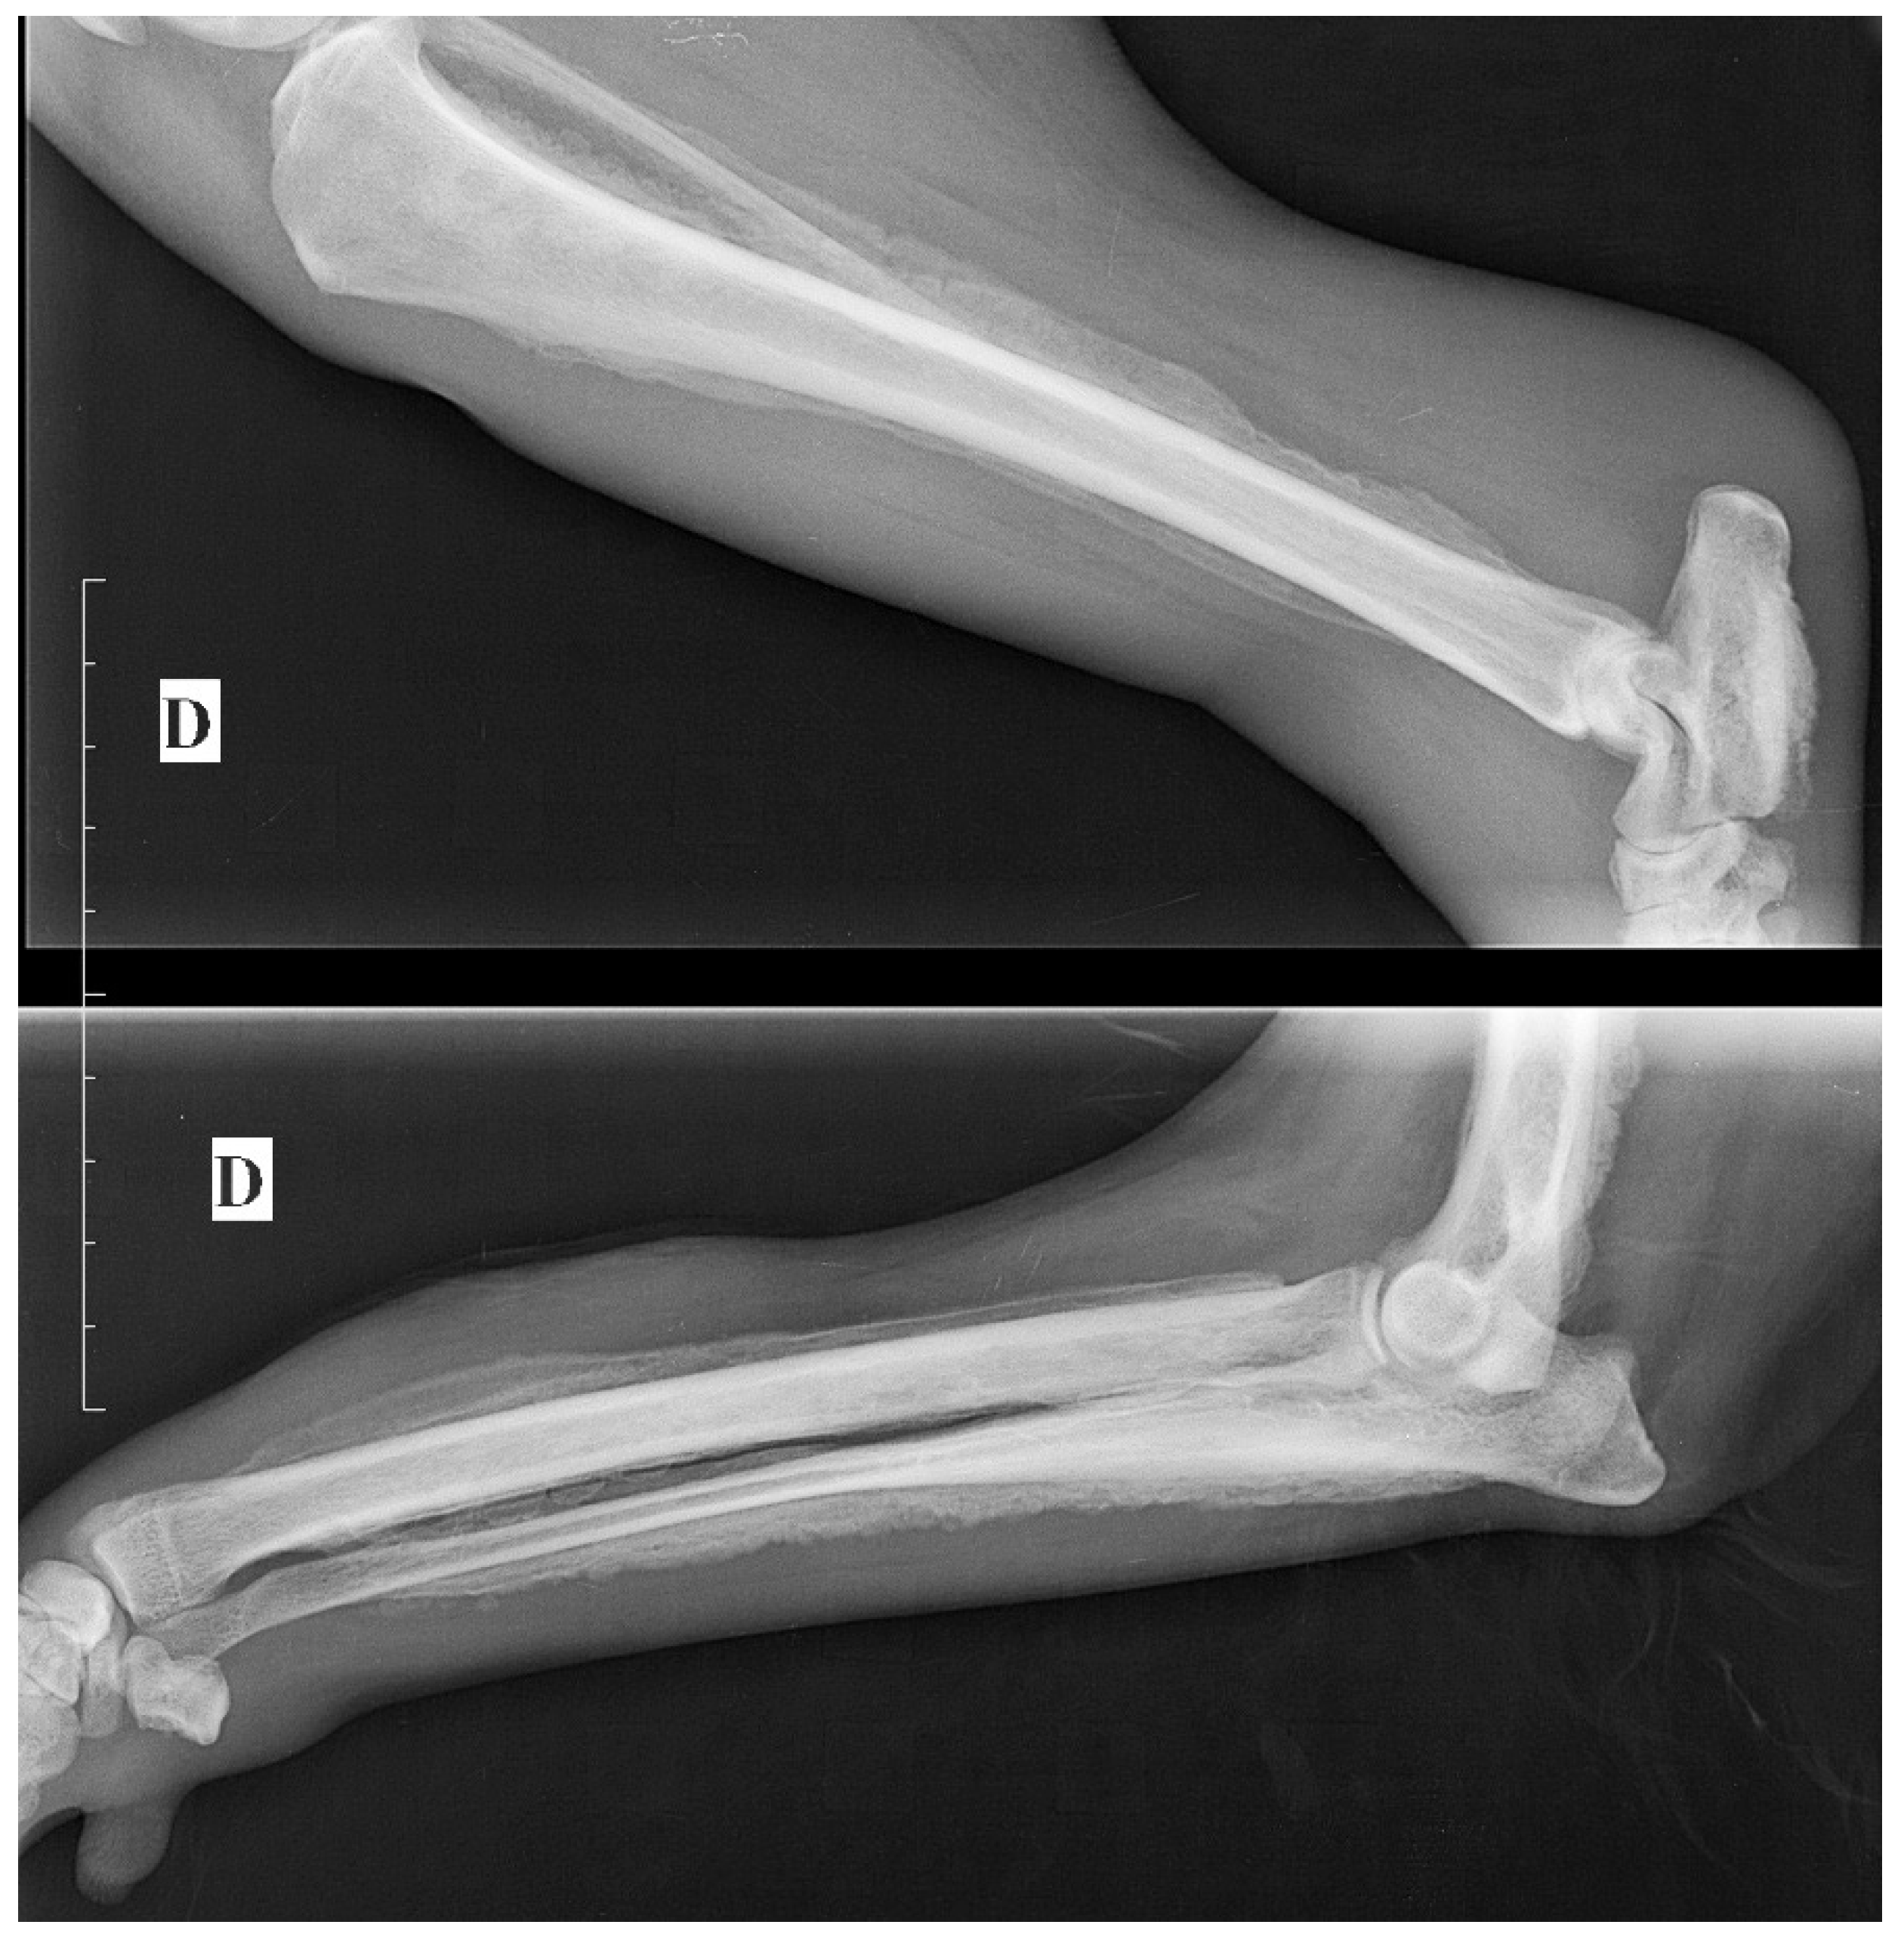

Abdominal ultrasonography revealed a small prostate of heterogeneous echogenicity associating hypoechoic foci and hyperechoic calcifications with acoustic shadowing (Figure 1), which was consistent with a tumor of the prostate. A 2.3-cm-thick mass had effaced the right iliac lymph node, causing compression of the caudal vena cava and aorta; the left iliac and hypogastric lymph nodes were enlarged. These images were compatible with lymph node metastases of prostatic cancer. The ventral edges of the vertebral bodies of L7 and L6 had marked irregularities compatible with bone metastases.

Castrated male dogs are at an increased risk of developing prostatic carcinoma [1]. A prostatic lesion with mineralization of the prostate in a dog neutered at a young age is highly suggestive of a tumor; in one study, 100% of neutered dogs with a lesion of the prostate with mineralization had neoplasia [6]. Ultrasound images of the prostate observed in the present case (irregular contours, parenchymal calcifications, presence of hypoechoic areas) are also characteristic of a neoplastic process. The lymph node and bone metastases strengthen this hypothesis.

Figure 1. Abdominal ultrasonography showing a small prostate of heterogeneous echogenicity associating hypoechoic foci and hyperechoic calcifications with acoustic shadowing consistent with a tumor of the prostate.